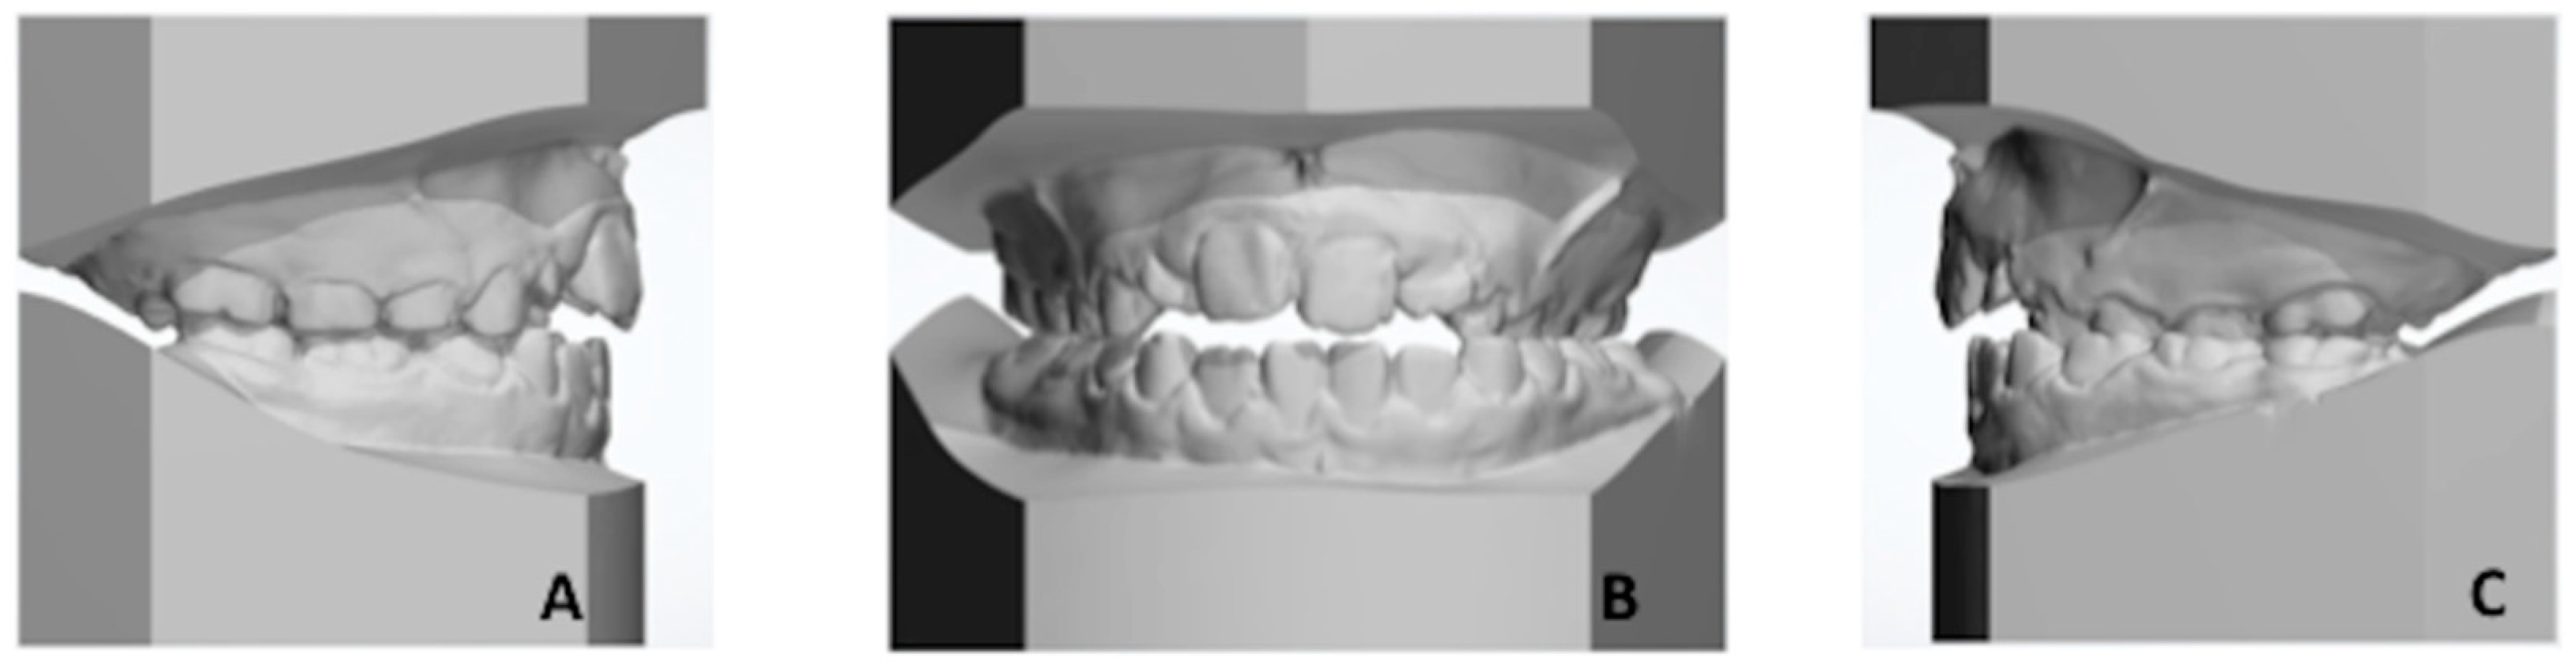

Digital models were registered and integrated within digital articulator in order to better assess the dento-alveolar relationship of both arches in centric occlusion (Figure 3) and centric relation (Figure 4).

Figure 3.

(A–C) Digital models in centric occlusion. (A) Right lateral view. (B) Frontal view shows the posterior crossbite at the left side with loss of coincidence between maxillary and mandibular midlines, due to a slight shift of the mandible toward the left side. (C) Left lateral view.

Centric occlusion (Figure 3) showed class I relationship on the right side and class II relationship (neutron-occlusion) on the left side. Such discrepancy was attributed to the slight mandibular shift upon closure due to potential occlusal interferences. In fact, when digital models were set in centric relation (Figure 4), i.e., with coincidence of both maxillary and mandibular midlines, posterior occlusal interferences were detected between vestibular cusps of primary molars and first permanent molars. These interferences could be due to a mild maxillary transverse constriction [4].